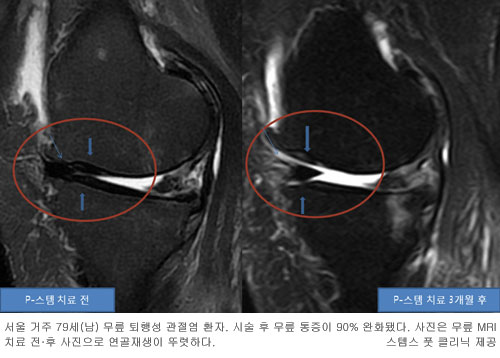

서울 청담동 스템스 풋 클리닉 김승현 원장은 “교정 깔창으로 무릎, 발, 다리의 얼라인먼트를 제대로 맞춘 후 지방줄기세포 PRP 혼합 연골재생 치료제로 연골재생과 더불어 무릎통증을 완화하고 무릎기능을 다시 찾을 수 있다”고 밝혔다.

또 “신발 교정 깔창과 자가 지방줄기세포, PRP 연골재생 치료는 비수술적인 방법이므로 큰 부작용이 없다는 것 또한 장점이라”고 덧붙였다.